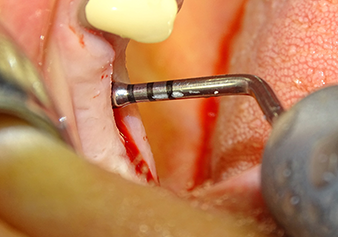

Following atraumatic preparation of the mucoperiosteal flap, the implant position was marked with the I1 instrument and the site prepared – until initial resistance was felt. Piezosurgical instruments were used in an up and down movement without any pressure being exerted. The piezoelectric vibration produced the desired and efficient cavitation.

The I2A instrument (diameter 2.0 mm) was then used to perforate the sinus floor intermittently and on the smallest scale possible. This special piezosurgical method ensures that the Schneiderian membrane is not damaged. When the Z25P was used, the membrane was already lifted slightly by the coolant supplied via the instrument tip (Fig. 3). The coolant quantity was just 50% in order to avoid high pressure in the implant bed.